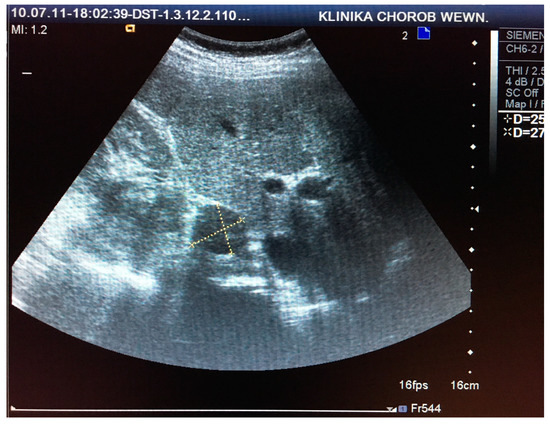

This retrospective study comprised 85 patients (71 women and 14 men) aged 30–81 (mean age 61 ± 16 years), who were hospitalized at the Department of Internal Medicine and Oncological Chemotherapy due to incidentally detected adrenal tumors in 2010 and 2011. Each patient underwent CT or MRI scans and US examinations before and after intravenous administration of SonoVue contrast (Bracco International B.V., Amsterdam, Netherlands) in two-dimensional (2D) and three-dimensional (3D) projections using Doppler techniques, as seen in Figure 1 and Figure 2. CT/MRI and US/CEUS examinations were performed at intervals of up to 6 weeks. US scanning was performed by a certified US specialist using a Siemens Acuson Antares instrument (Siemens Medical Solutions USA, Inc. Mountain View, CA 94043, USA) with a 2–6 MHz convex transducer. Based on the performed imaging, hormonal tests, and pathological evaluation of oligobiopsy, 81 incidentalomas, 2 pheochromocytomas, 1 case of adrenocortical carcinoma, and 1 liver cyst were diagnosed.

Figure 1. Visualization and measurement of adrenal tumor in two-dimensional (2D) ultrasound (US) examination.